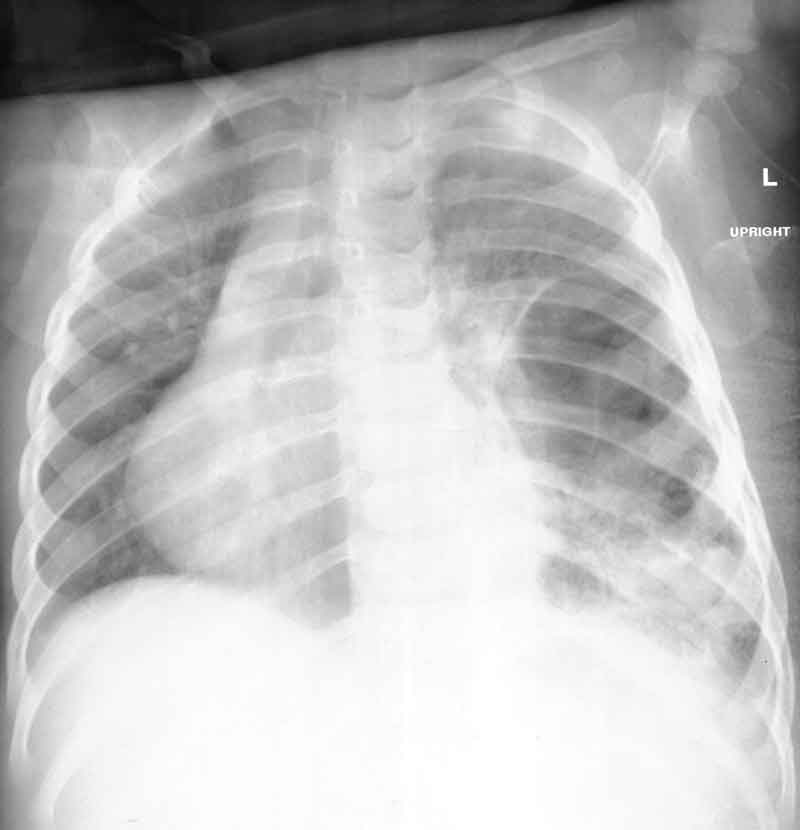

ANSWER

At this time, our group entertained the following possibilities:1. pneumonia with pleural effusion, perhaps an empyema

2. lung abscess

3. infected peumatocele

4. diaphragmatic hernia

5. infected congenital cyst

The girl was moderately distressed, with a respiratory rate of 60/minute, an oxygen saturation of 88%, and decreased breath sounds on left side.The

staff at the regional hospital inserted a chest tube and electively

ventilated her using low support for one night. They drained 50 ml of

pus form the cavity which was sent for Gram stain and culture. Initial

investigation included: WBC:7.3 bands: 1.3, Hb: 104 , platelets: 519,000,

and blood culture. Clindamycin and cefotaxime were initiated intravenously.